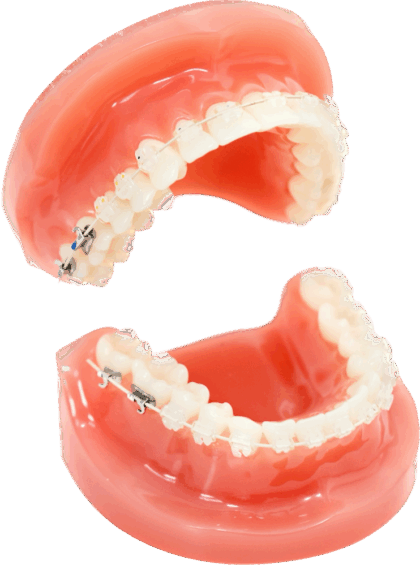

当院でおこなっているマウスピース矯正

インビザライン・ファースト

インビザライン・ファーストは、歯の生え変わり途中にあるお子さま(混合歯列期)を対象に行うマウスピース矯正です。透明で目立ちにくいオーダーメイドのマウスピースを1〜2週間ごとに交換し、歯並びを整えていきます。装着中でも目立ちにくいため、見た目を気にせず治療を進められるのが大きな特徴です。

また、インビザライン・ファーストでは「顎の幅を広げる治療」と「歯の位置を整える治療」を同時に行うことができます。

プレオルソ

プレオルソは、成長期のお子さまの歯並びや噛み合わせを整えるために使用する取り外し式のマウスピース型の装置です。やわらかく弾力のある素材で作られており、お子さまのお口への負担が少なく、無理なく矯正治療を進められるのが特徴です。学校から帰宅後や就寝時にのみ装着し、日中の学校生活などでは外しておくことができます。

ムーシールド

ムーシールドは、主に子どもの「受け口(反対咬合)」を改善するためのマウスピース型の矯正装置です。やわらかい素材で作られているため、お子さまの負担が少なく、違和感も少ないのが特徴です。就寝時に装着するだけで、下顎の成長を穏やかにコントロールし、自然な噛み合わせに導きます。